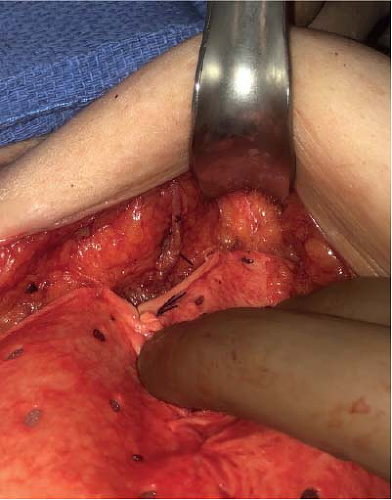

After mastectomy, the remaining breast skin flaps are dependent on the subdermal plexus as well as perforators in the subcutaneous plane for perfusion (Fig. 18-2) (4,5,6). Anatomic dissection at the level of the breast capsule maximizes oncologic resection of the breast gland while also minimizing trauma to the skin flaps, thereby optimizing perfusion. Mastectomy dissection in a plane deep to the breast capsule thus risks incomplete oncologic resection. Meanwhile, overaggressive suprafascial dissection compromises blood flow to the mastectomy flap, risking ischemia changes with no oncologic advantage, as taking tissue above the breast gland offers no survival benefit (7).

![]() FIGURE 18-2 Intraoperative view of a subcutaneous perforator supplying the subdermal plexus after mastectomy performed in the anatomic plane of the breast capsule. |